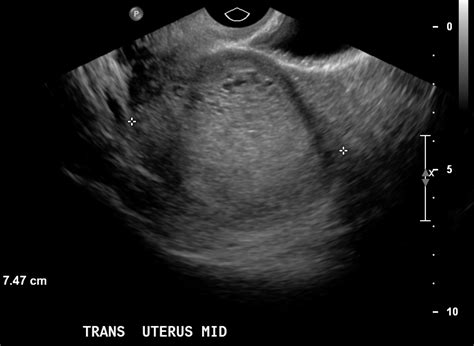

The molar pregnancy ultrasound is the gold standard for early detection. When a healthcare provider notices symptoms like vaginal bleeding, severe nausea, or a uterus that is larger than expected for the gestational age, they will order an ultrasound scan. This diagnostic imaging allows the doctor to visualize the contents of the uterus in real-time.

During the scan, a sonographer or radiologist uses high-frequency sound waves to create images of the uterine cavity. In a healthy pregnancy, the ultrasound will show a clear gestational sac with a developing fetus. In contrast, the imaging of a molar pregnancy displays distinct patterns that deviate from normal development.